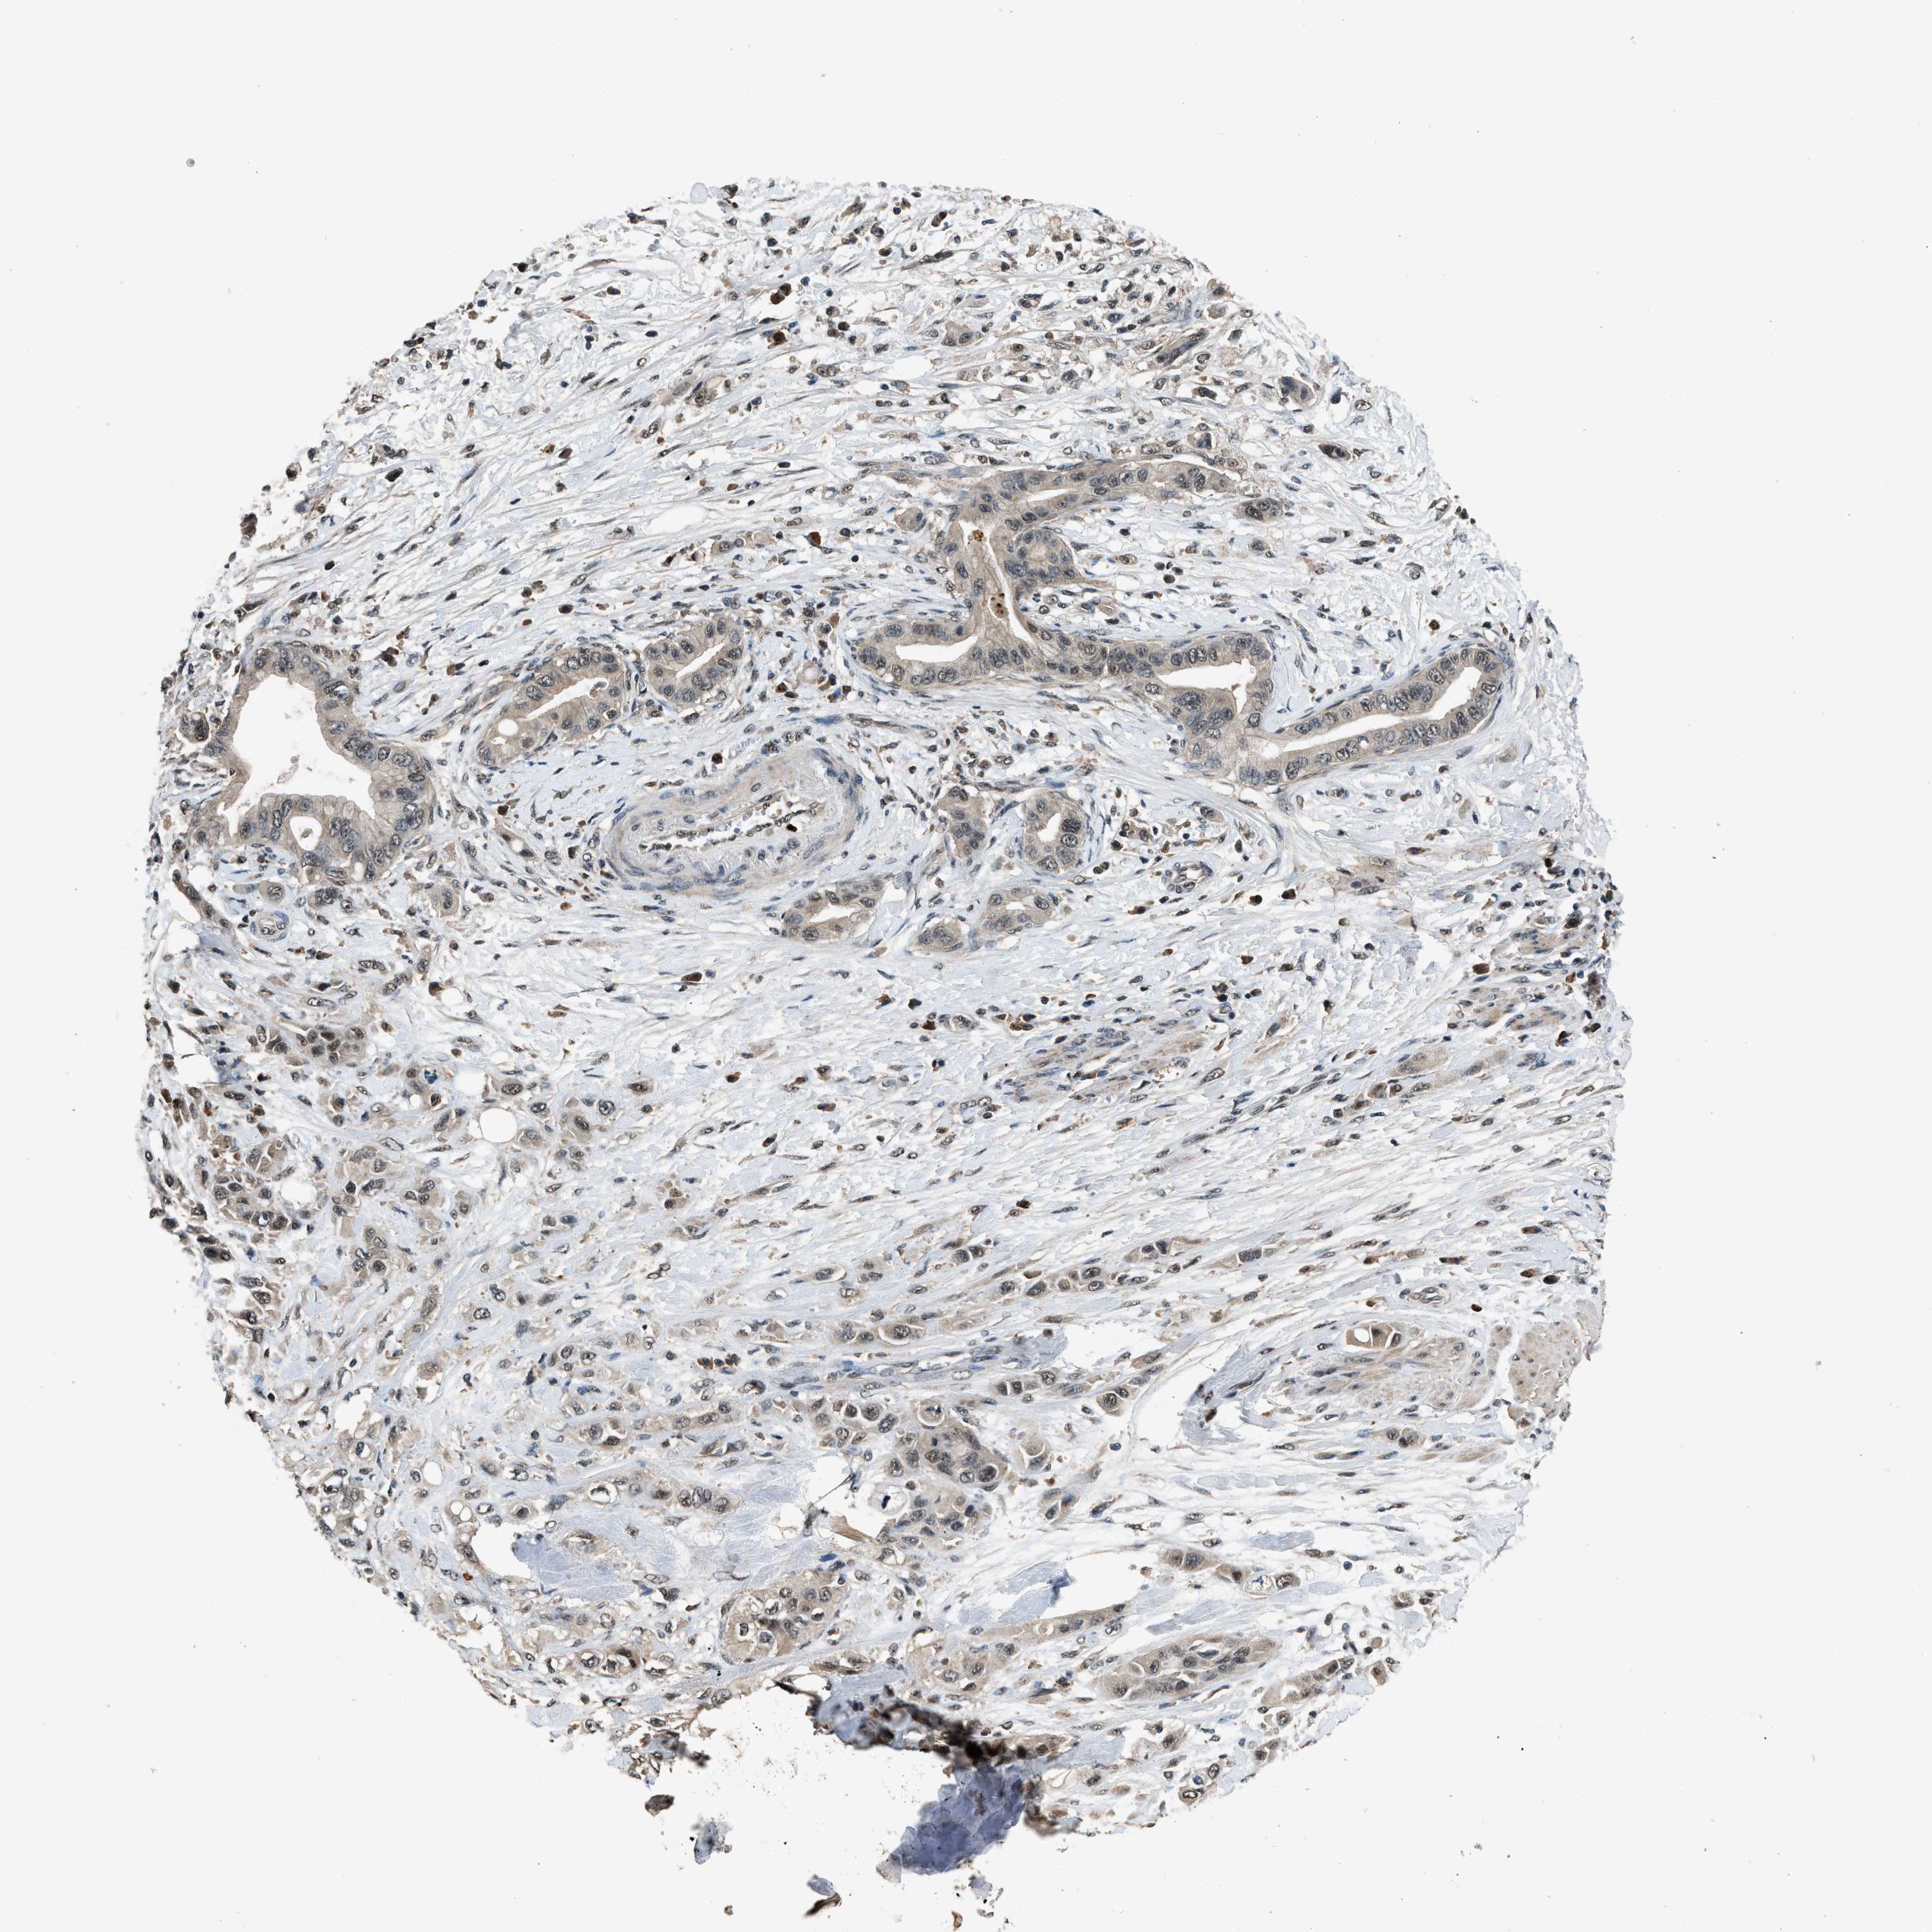

PANCREATIC CANCER - Protein expressioni

A mouse-over function shows sample information and annotation data. Click on an image to view it in a full screen mode. Samples can be filtered based on level of antibody staining by selecting one or several of the following categories: high, medium, low and not detected. The assay and annotation is described here.

Note that samples used for immunohistochemistry by the Human Protein Atlas do not correspond to samples in the TCGA dataset.

Antibody stainingi

Antibody staining in the annotated cell types in the current human tissue is reported as not detected, low, medium, or high, based on conventional immunohistochemistry profiling in selected tissues. This score is based on the combination of the staining intensity and fraction of stained cells.

Each image is clickable and will lead to virtual microscopy that enables deeper exploration of all samples and also displays staining intensity scores, fraction scores and subcellular localization as well as patient and tissue information for each sample.

Antibody HPA016713

Staining

High

Medium

Low

Not detected

Intensity

Strong

Moderate

Weak

Negative

Quantity

>75%

75%-25%

<25%

None

Location

Nuclear

Cytoplasmic/membranous

Cytoplasmic/membranous,nuclear

Adenocarcinoma, NOS